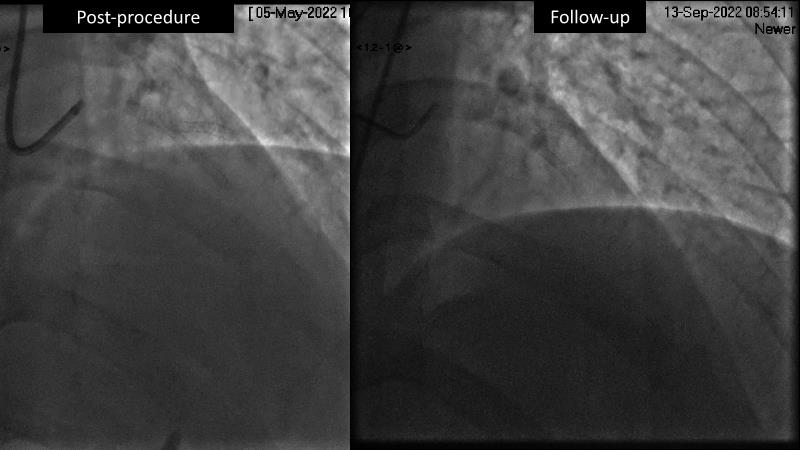

- To learn the utility of the DCB for PCI in a variety of lesion and patient subsets

- To understand the evidence and outcomes of this DCB in real world patients